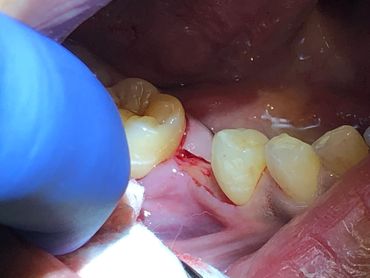

The Neodent GM Guided Surgery Kit is a compact, easy to use guided surgery system. Clinicians can provide CT scan, digital photos, and impressions to a laboratory for precise implant guide fabrication. Temporary teeth can be made and the lab will know the depth, angle, and timing of the connection of the implant. This allows you better esthetics and provides the patient teeth the same day with less chair time.